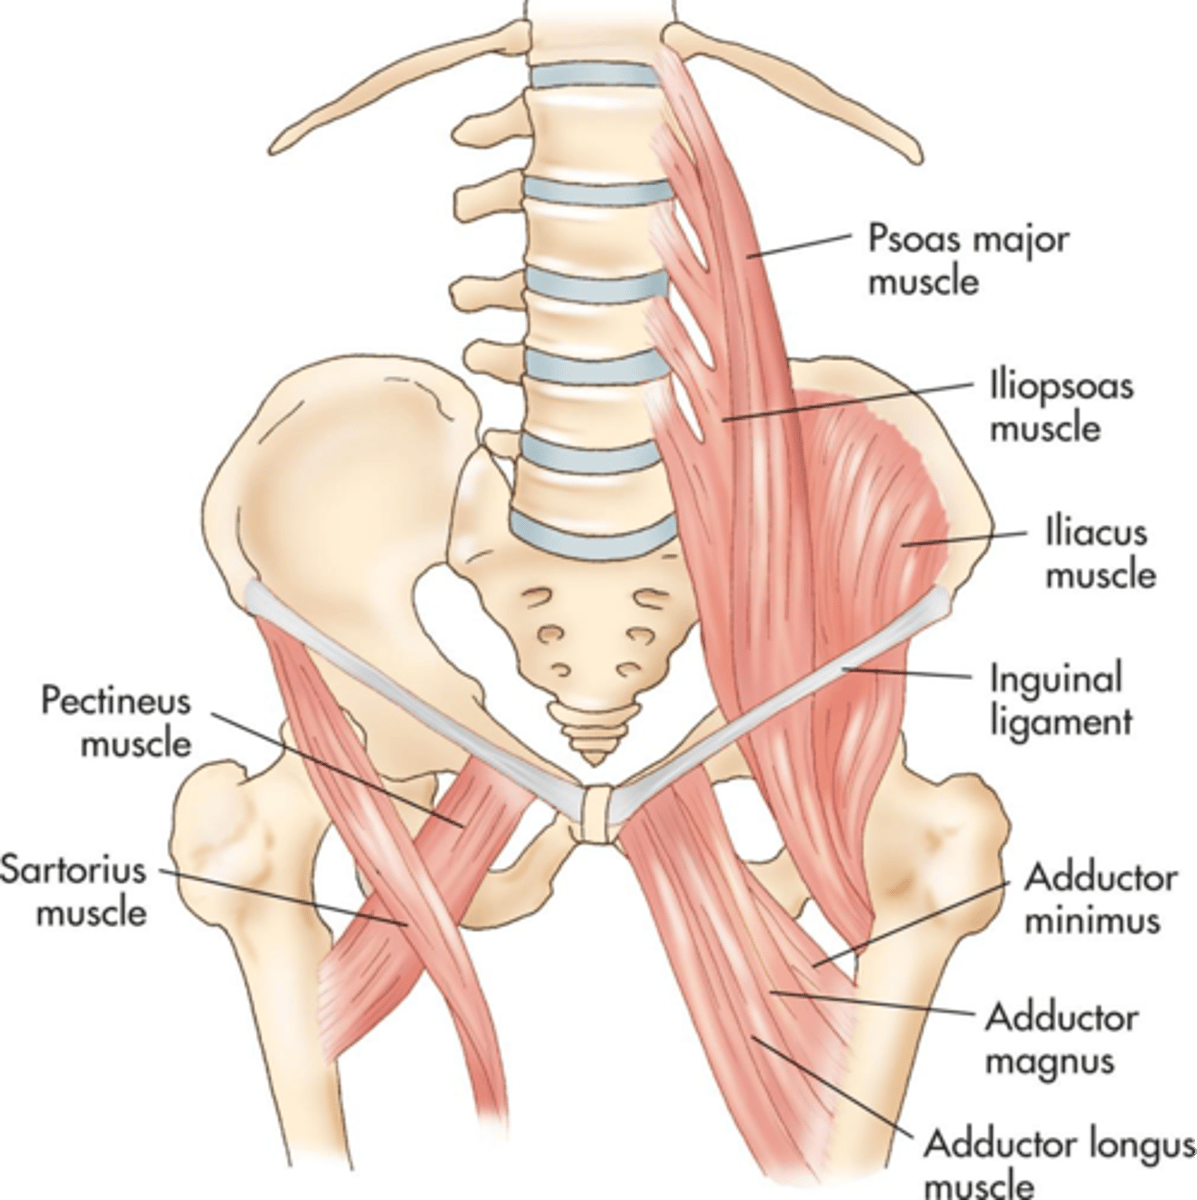

Psoas muscles extend from the ___ aspects of the lumbar vertebrae across the ___ abdominal wall to the ___

lateral; posterior; iliac crest

Illiopsoas muscles travel ___ from the psoas to insert into the ___ of the femur

anteroinferior; lesser trochanter

Obturator internus muscles line the ___ walls of the true pelvis

lateral

Piriformis muscles are in the ___ region of the true pelvis behind the ___

posterior; uterus

What muscle is often mistaken for ovaries?

piriformis